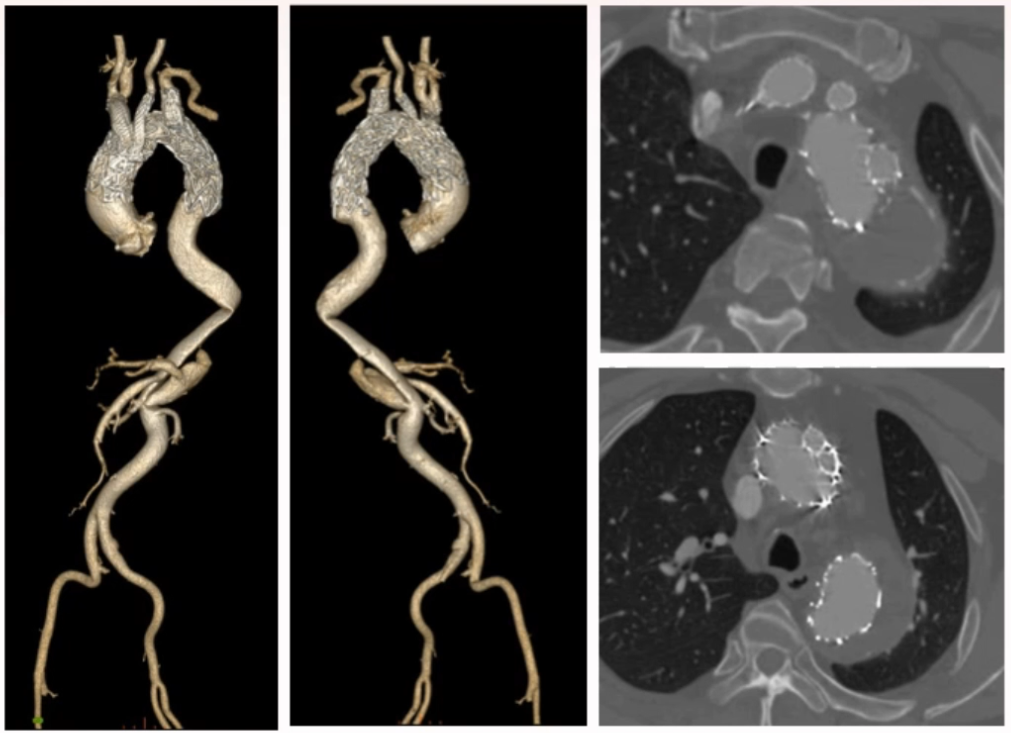

术前影像

术前CT呈现典型慢性夹层动脉瘤特征,近端有一枚支架,支架开口位于左锁骨下动脉开口以远,假腔内有造影剂,属于 Ia 型内漏;远端破口位于内脏动脉区,腹主动脉段无假腔,近端胸主动脉夹层动脉瘤最大直径 58 mm,手术指征明确。

术后复查

术后一周 CT 复查结果令人满意,整个支架形态良好,三分支通畅,Ia 型内漏完全消失,胸主动脉上段基本血栓化。因为内脏区域破口的存在,胸主动脉远端假腔仍有造影剂痕迹,但这并不影响整体手术效果。